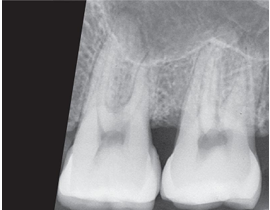

What is the problem with this OVERDEVELOPED FILM X-ray?

Appears dark, Excessive developing time, Developer solution too hot, Inaccurate timer or thermometer, Concentrated developer solution

How would you resolve this OVERDEVELOPED FILM X-ray?

Check development time • Check developer temperature • Replace faulty timer or thermometer • Replenish developer with fresh solutions as needed